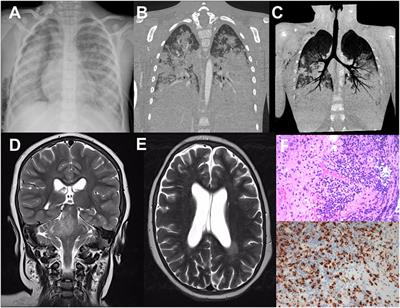

Congenital medulloblastoma in two brothers with SUFU-mutated Gorlin-Goltz syndrome: Case reports and literature review

Case Report